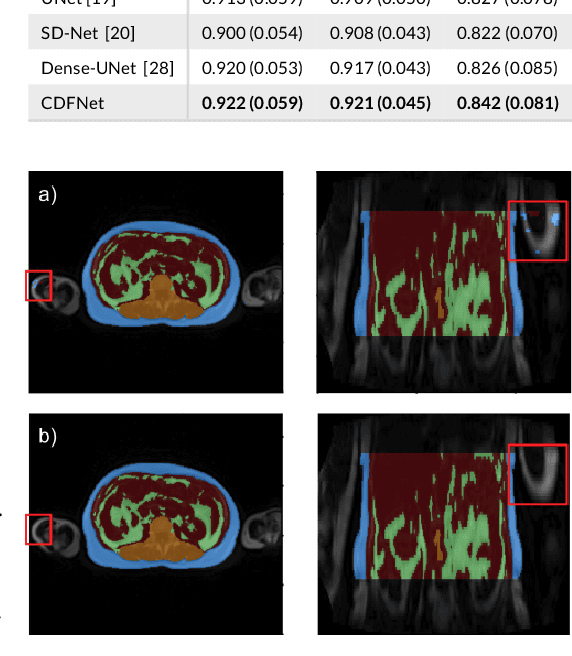

Abstract:Purpose: Development of a fast and fully automated deep learning pipeline (FatSegNet) to accurately identify, segment, and quantify abdominal adipose tissue on Dixon MRI from the Rhineland Study - a large prospective population-based study. Method: FatSegNet is composed of three stages: (i) consistent localization of the abdominal region using two 2D-Competitive Dense Fully Convolutional Networks (CDFNet), (ii) segmentation of adipose tissue on three views by independent CDFNets, and (iii) view aggregation. FatSegNet is trained with 33 manually annotated subjects, and validated by: 1) comparison of segmentation accuracy against a testingset covering a wide range of body mass index (BMI), 2) test-retest reliability, and 3) robustness in a large cohort study. Results: The CDFNet demonstrates increased robustness compared to traditional deep learning networks. FatSegNet dice score outperforms manual raters on the abdominal visceral adipose tissue (VAT, 0.828 vs. 0.788), and produces comparable results on subcutaneous adipose tissue (SAT, 0.973 vs. 0.982). The pipeline has very small test-retest absolute percentage difference and excellent agreement between scan sessions (VAT: APD = 2.957%, ICC=0.998 and SAT: APD= 3.254%, ICC=0.996). Conclusion: FatSegNet can reliably analyze a 3D Dixon MRI in1 min. It generalizes well to different body shapes, sensitively replicates known VAT and SAT volume effects in a large cohort study, and permits localized analysis of fat compartments.

Abstract:Increased information sharing through short and long-range skip connections between layers in fully convolutional networks have demonstrated significant improvement in performance for semantic segmentation. In this paper, we propose Competitive Dense Fully Convolutional Networks (CDFNet) by introducing competitive maxout activations in place of naive feature concatenation for inducing competition amongst layers. Within CDFNet, we propose two architectural contributions, namely competitive dense block (CDB) and competitive unpooling block (CUB) to induce competition at local and global scales for short and long-range skip connections respectively. This extension is demonstrated to boost learning of specialized sub-networks targeted at segmenting specific anatomies, which in turn eases the training of complex tasks. We present the proof-of-concept on the challenging task of whole body segmentation in the publicly available VISCERAL benchmark and demonstrate improved performance over multiple learning and registration based state-of-the-art methods.